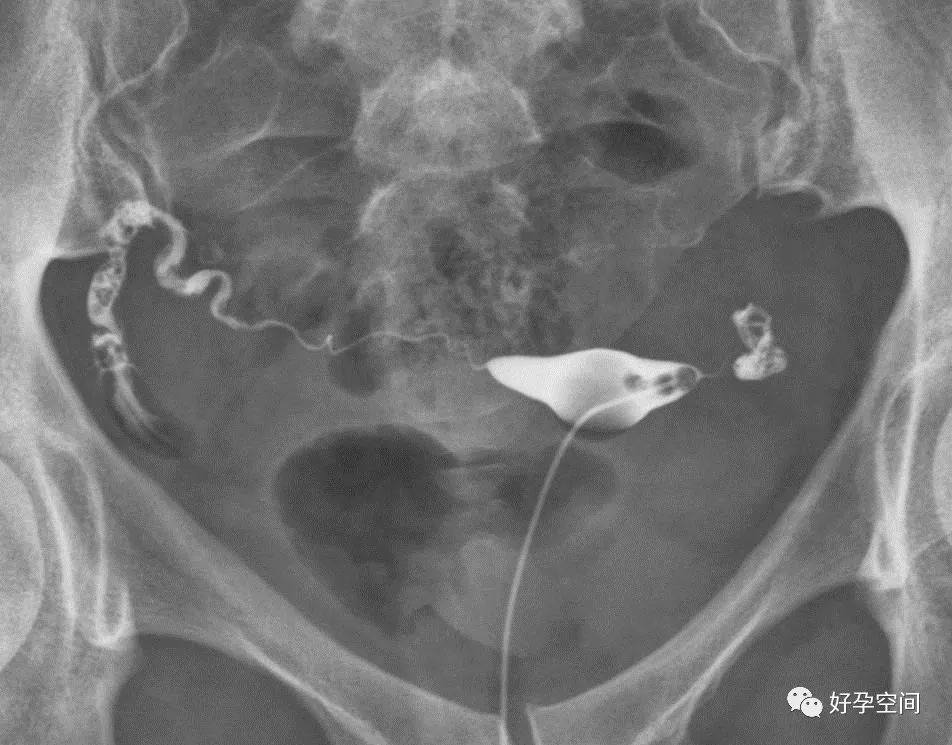

双侧输卵管上行